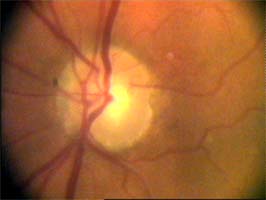

Tento terč má širokou cirkulární peripapilární atrofii, která opticky vytváří falešný dojem širokého neuroretinálního lemu, zvláště nasálně.

Očekávali byste protažení exkavace k hornímu pólu terče, jak nám ukazuje tento snímek z tomografu HRT II.

Co je příčinou toho, že při pohledu na snímky hodnotíme rozsah exkavace nesprávně? Je to skutečnost, že i růžová oblast neuroretinálního lemu může být již prohloubená, což vídáme zvláště na počátku rozvoje glaukomové neuropathie.

A jak se můžeme vyhnout záměně okrsku bledší barvy za skutečnou exkavaci? Tím, že budeme mít na paměti, že exkavace může být větší než nablednutí. Také zařazení zeleného filtru na pomůže snížit nežádoucí barevný kontrast.